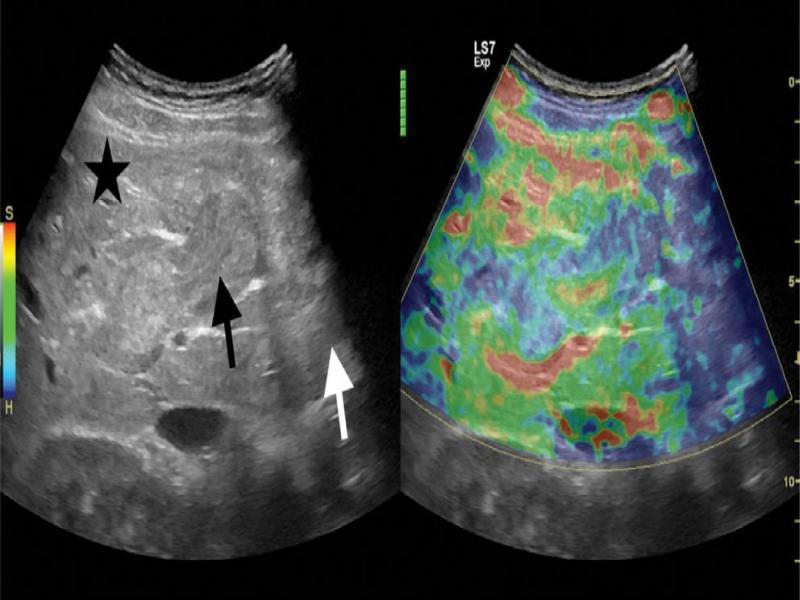

Fig. 4.

On sonoelastographic image, normal parenchyma is coded in red-green color (star mark), whereas portal vein tumor thrombosis and the affected left lobe parenchyma are coded in blue-green (black arrow) and pure blue color (white arrow), respectively. Based on the color bar on the left side, red color reflects less stiff tissue, while blue color reflects more stiff tissue than the rest. Besides, green color reflects medium-stiff tissue